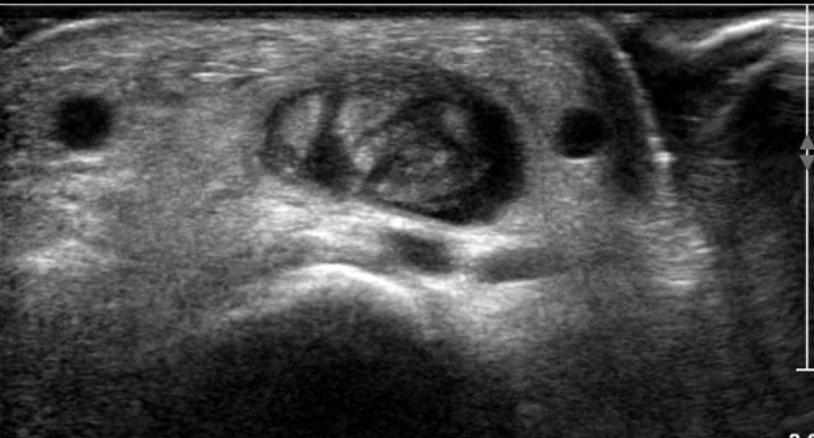

US tenosinovitis de Quervain

Engrosamiento de tendones y retinaculo

Liquido en su vaina